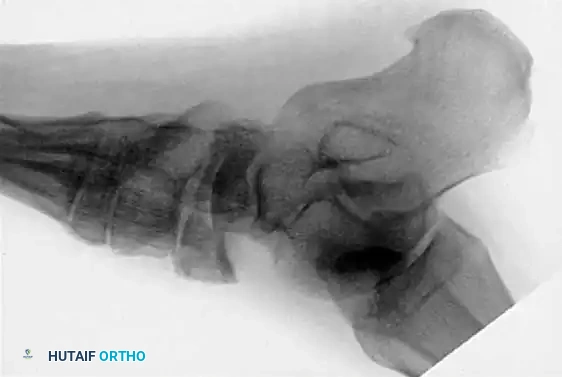

Fig. 86-36 Open reduction and internal fi xation of type III navicular fracture. A and B, Preoperative radiographs. C, Semicoronal CT scan showing comminution of body of navicular. D and E, Postoperative radiographs.

Fig. 86-36: Open reduction and internal fixation of a Type III navicular fracture. Note the severe comminution on the preoperative CT and the restoration of the medial column length postoperatively.